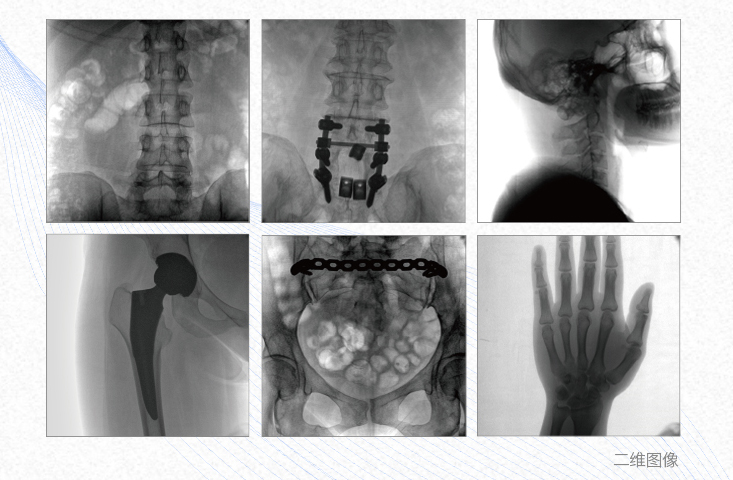

有效重建復雜的脊柱三維模型,提供準確的二維、三維圖像,提高螺釘植入的準確性,縮短手術時間,減少并發癥的概率,降低輻射的攝入。

3、關節外科

主要應用于肩關節、肘關節、髖關節、膝關節的關節置換及解剖復位的定位。它可以準確地置入假體,減少輻射時間,降低輻射劑量。

術中三維成像和橫斷面圖像提供多角度的手術診斷信息,輔助醫生進行術中評估判斷,諸如骨折復位情況和內植入螺釘的尺寸和位置,輔助手術更好地完成。

提供更大的術中三維成像視野,采集更多圖像信息,可一次拍全全段頸椎、全段腰椎、七節胸椎、雙側骶髂關節、股骨頭及單側盆骨。